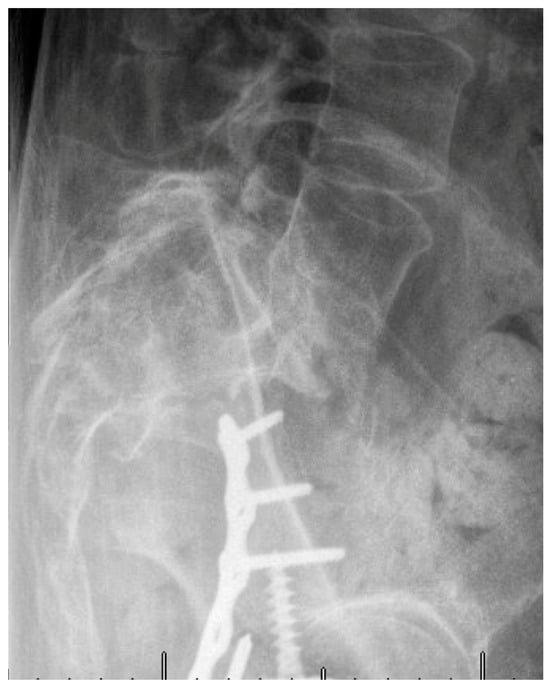

Minimally Invasive and Navigation-Assisted Fracture Stabilization Following Traumatic Spinopelvic Dissociation

4. Evolution of Open Surgery to Minimally Invasive Techniques for Lumbopelvic Fixation

5. Techniques and Considerations in Spinopelvic Fixation: Sequence, Reduction, and Avoiding Complications

6. Spinopelvic Fixation Percutaneous Technique